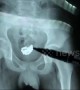

Occurred on May 20, 2019 / Ben Tre, Vietnam

Info from Licensor: "Lottery dogs help employers with disabilities to earn extra income to cover day-to-day living."